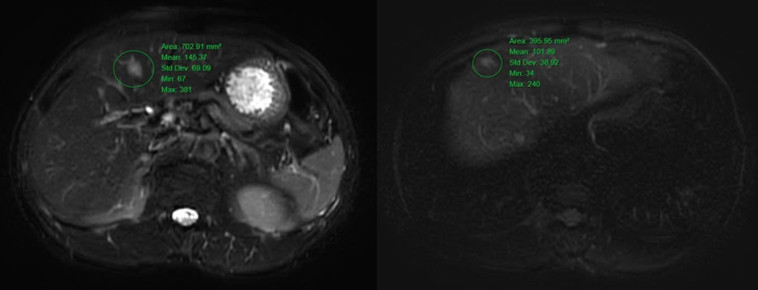

- Hình ảnh nốt giảm tỷ trọng ở nhu mô gan hạ phân thùy IV, tăng nhẹ chuyển hóa FDG (SUVmax: 2.76). Cần phối hợp đánh giá thêm.

Hình 5. Hình ảnh các nốt tổn thương nhu mô gan hai bên tăng tín hiệu trên xung T2W cộng hưởng từ ổ bụng, hạn chế khuếch tán ở nốt hạ phân thùy V (vòng tròn màu xanh lá cây) kích thước lớn nhất ~ 14x16mm.

Kết quả PET/CT toàn thân của bệnh nhân tuy không phát hiện được tổn thương nguyên phát, nhưng phát hiện được rất nhiều các tổn thương di căn hạch trong ổ bụng-tiểu khung như nhiều hạch cạnh động mạch chủ, hạch dọc bó mạch chậu 2 bên với kích thước lớn và SUVmax cao, ngoài ra còn có xương đốt sống, cánh chậu, và gan. Với những thông tin có được từ PET/CT, bác sĩ lâm sàng có thể lựa chọn các vị trí khác nhau để sinh thiết lại tổn thương tìm nguồn gốc u (ví dụ: xương, gan). Đồng thời cũng đặt ra cân nhắc về nội soi tai mũi họng lần thứ hai để khẳng định lại tính chất của tổn thương amidan phải phát hiện trên PET/CT nhưng chưa nhìn được trong nội soi tai mũi họng lần đầu tiên.

Bệnh nhân này đã được hội chẩn hội đồng toàn trung tâm, có chỉ định lấy trọn hạch bẹn đánh giá lại nhằm loại trừ các trường hợp U lympho thường khó xác định trên mô bệnh học với bệnh phẩm lấy bằng phương pháp sinh thiết kim, đồng thời chỉ định nội soi đại tràng lần thứ hai nhằm cẩn trọng loại trừ lại tổn thương nguyên phát tại đại tràng trong trường hợp. Hiện tại, bệnh nhân này hiện vẫn đang tiếp tục được khảo sát thêm sự hiện diện của tế bào ung thư tại các cơ quan khác bằng các phương pháp sinh thiết xương (cánh chậu), sinh thiết khối giảm tỷ trọng tại gan, đồng thời khảo sát lại các cơ quan mà FDG-PET thường hạn chế đánh giá như hệ tiết niệu – bàng quang, bằng các xét nghiệm tế bào học nước tiểu, nội soi bàng quang – niệu quản ngược dòng để tìm ra nguồn gốc nguyên phát của ung thư.